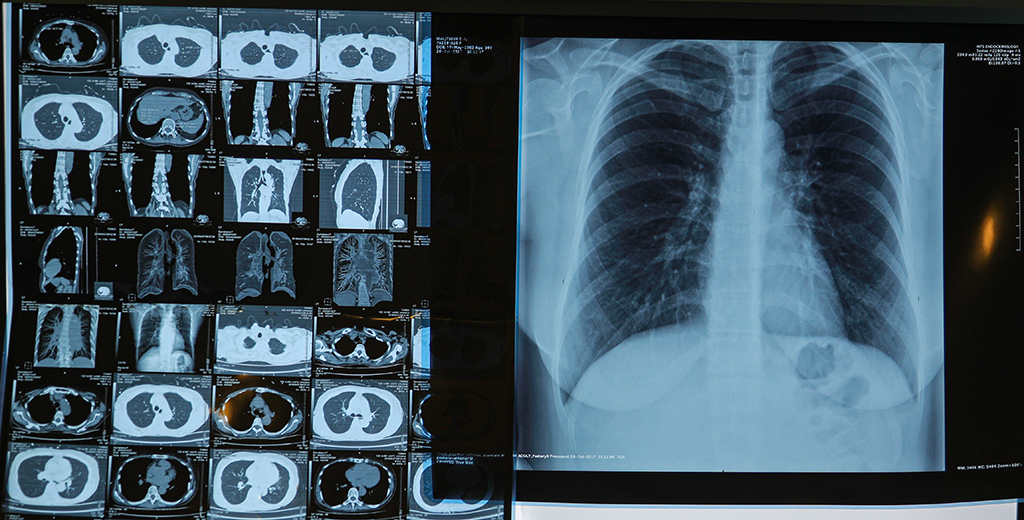

47 человек умерли в США из-за вызванного курением вейпов и электронных сигарет заболевания лёгких. Ещё 2290 человек проходят лечение, сообщили в центрах по контролю и профилактике заболеваний.

Случаи летальных исходов были зафиксированы в 25 штатах и округе Колумбия. Загадочное лёгочное заболевание выявлено у жителей 49 из 50 штатов (все штаты за исключением Аляски), округа Колумбия и двух территорий, находящихся под управлением США, сказано в пресс-релизе.

Все пострадавшие пользовались электронными сигаретами или вейпами.